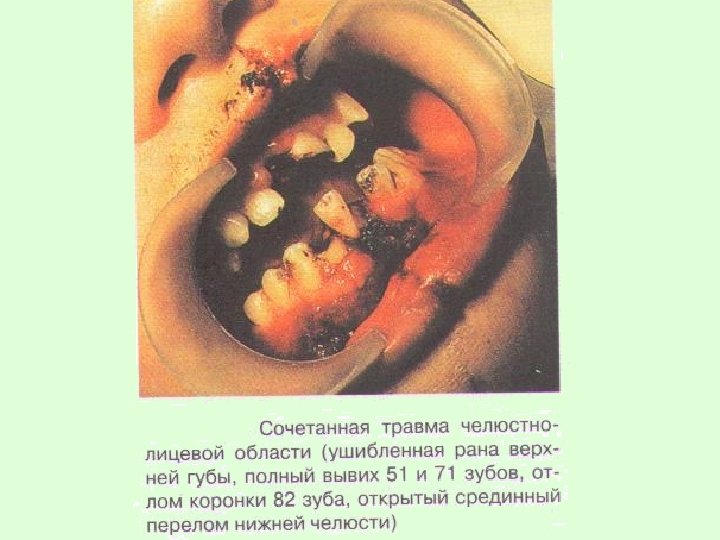

У детей сочетанные повреждения чаще всего возникают в результате автокатастроф, падения с высоты, во время спортивных занятий и характеризуются переломами челюстей, травмами зубов, гематомами мягких тканей.

Каждая из составляющих сочетанной травмы отягощает течение процесса выздоровления. Кроме того, при сочетании травмы челюстей с ранами, сопровождающимися дефектами тканей, или лоскутными ранами возникает угроза развитияразличных видов асфиксий.

Поэтому правильные действия врача на догоспитальном этане при оказании помощи имеют важное значение для предотвращения угрожающих жизни ребенка осложнений.